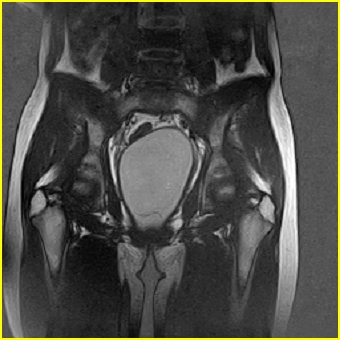

女、15岁、下腹疼痛2天,排尿困难1天。查体:处女膜闭锁,距处女膜约4至5cm处扪及一约5cm直径的圆形包块,张力较高,触痛明显、欠活动。b超提示子宫增大伴宫内增强回声团。

影像意见:子宫直肠陷凹积血。

更正影像意见:阴道积血。

处女膜闭锁,阴道积血,子宫积血.

子宫及阴道积血。

处女膜闭锁,伴子宫及阴道积血.